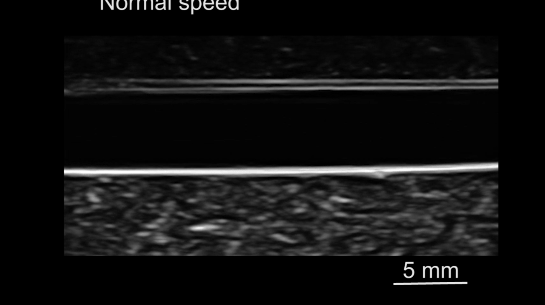

由于微型机器人在人体内的成像和导航是无线医疗机器人临床应用中的一个关键挑战,研究人员使用了超声设备,将磁驱软体鱼放置在血管模型内,使用超声设备对软体鱼进行成像和监测,并由频率为30赫兹、振荡角度为30°的振荡磁场驱动。

从下图可以看出,磁驱软体鱼可以在超声成像下游过血管。

超声波引导磁驱软体鱼运动。